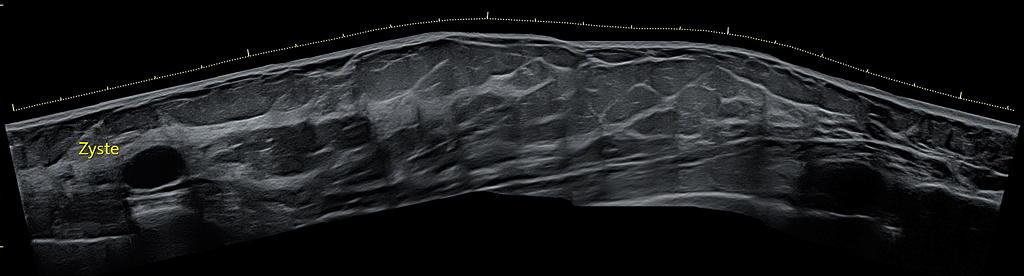

Panoramascan (Siescape)

Der Panorama-Scan ermöglicht die Erstellung eines zweidimensionalen Übersichtsbildes, das die Lagebeziehung eines Herdes zu anderen Strukturen in der Brust (z.B. Mamille oder Brustmuskel) aufzeigt. Bei mehreren Herden (Multifokalität) kann auch die Lage dieser Herde zueinander aufzeigt werden. Sind Herdbefunde sehr groß, kann deren gesamte Ausdehnung besser erfasst werden.